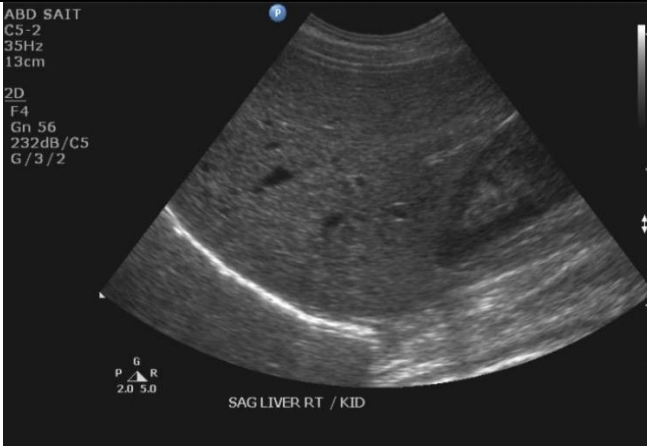

19

Q

What term best describes the echogenicity of the liver?

A

Hyperechoic to the kidney